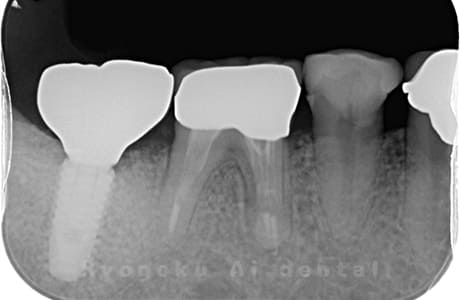

Case07

-

- 原因

- 右下6番歯根破折

- 治療内容

- インプラント治療

- 治療費用

- 約600,000円

右下の腫れが治らないとの事でご来院された患者様です。歯が割れていたため、抜歯を行い、骨に代わるお薬を入れ、インプラントを埋入致しました。経過良好で大変満足していただけました。

<リスク・副作用>

治療後、痛みや違和感、出血、腫れなどが出る事があります。喫煙者、糖尿病などの方の場合、歯が生着しない場合があります。